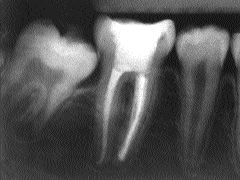

Final endo x-ray.